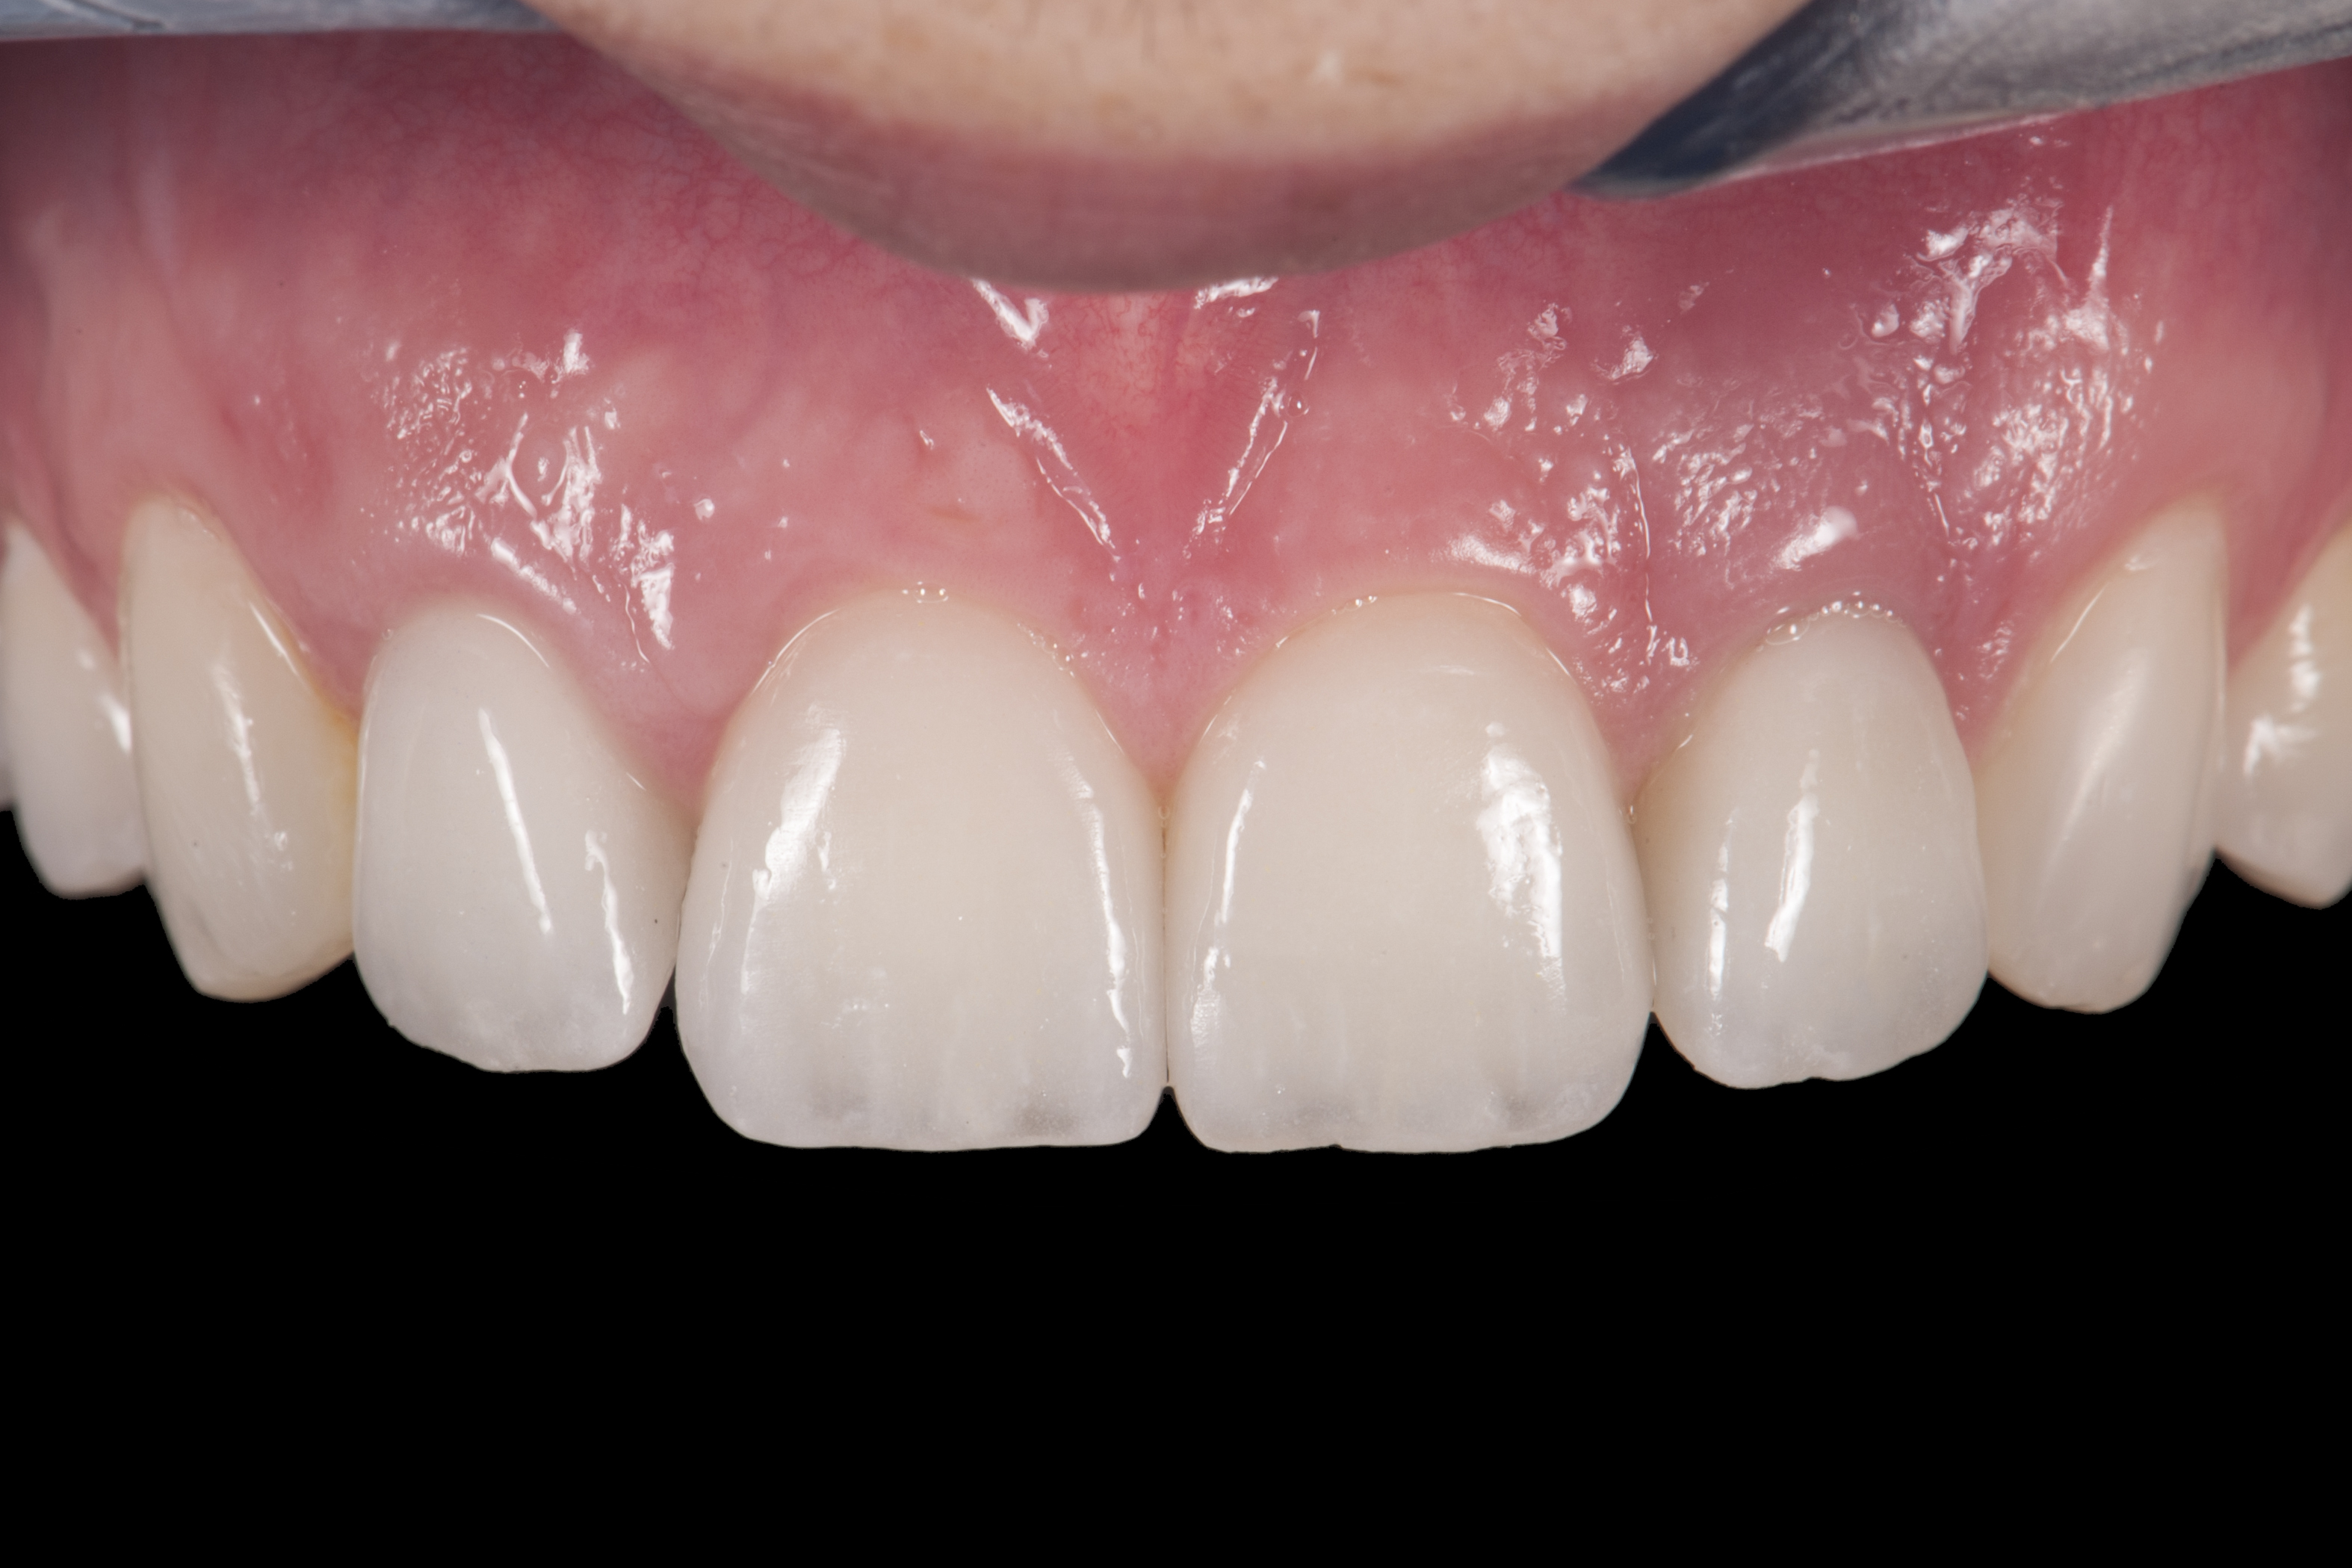

(14.) Occlusal view. Some form of augmentation would be needed if implants were being considered.

Figure 14

Some patients do not want an implant due to the need for surgical intervention, and others may not have enough space for implant placement. A 15-year-old patient presented to the office after completion of orthodontic treatment to idealize the spacing of her teeth and improve her occlusal relationship (Figure 12 through Figure 14). Because both of her maxillary lateral incisors were missing, the patient was wearing a retainer with lateral incisor pontics. She had a busy school schedule, but expressed her desire for a fixed restorative option. All of her options were discussed, and the patient was informed that if she wanted an implant, she would have to wait for at least 3 to 4 years for completion of growth. The patient was not sure if or when she wanted to have an implant placed in the future, especially considering her busy schedule and desire to attend college after high school. Considering her age and the need to be conservative, a single-wing zirconia Maryland Bridge was chosen as the ideal prosthetic replacement option. Because bonding a non-etchable and smooth surface such as zirconia requires chemical adhesion, it was decided to use a modified technique to make the bridge more retentive. One of the ways to improve adhesion of a zirconia bridge is to use an etchable feldspathic ceramic layer on the internal surface of the zirconia retainer.56-58 Unfortunately, it can be difficult to determine the thickness of the ceramic and ensure accurate seating of the restoration.